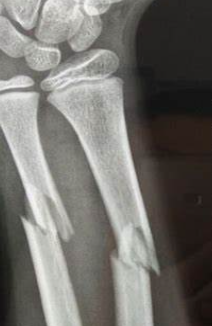

近日,12岁男孩小晟(化名)在运动时不小心受伤,左手臂剧痛难忍,在家附近的医院一检查,发现尺桡骨干双骨折。

儿童桡尺骨骨折(示意图)

按照传统治疗方案,手术需要在X射线下进行,还要开刀打入钢板固定,术后会留下约5厘米长的刀口。